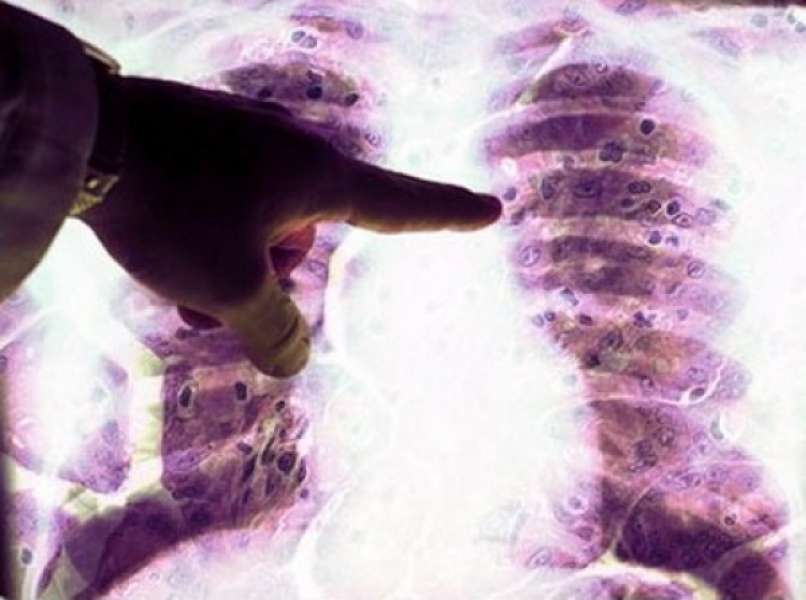

Kot je na mednarodnem posvetu o azbestu v Goriških brdih povedala prof. dr. Metoda Dodič Fikfak iz univerzitetnega kliničnega centra, je v zadnjih nekaj letih pri nas okoli 30 ljudi na novo obolelo za mezoteliomom, najhujšo obliko bolezni, ki jo povzroča azbest. Strokovnjaki so navedli še eno grozljivo dejstvo: da je rakavih bolezni okrog industrijskih centrov, kjer se je ta material uporabljal, največ.

Azbest povzroča številne bolezni, kot so azbestoza, plevralni plaki, plevralni izliv, mezoteliom in pljučni rak, pa tudi raka ovarija in grla. »Je ena redkih, če ne edina snov, ki povzroča raka na tako številnih organih, zato mu pravimo ubikvitarni karcinogen,« je na posvetu opozorila Dodič Fikfakova.